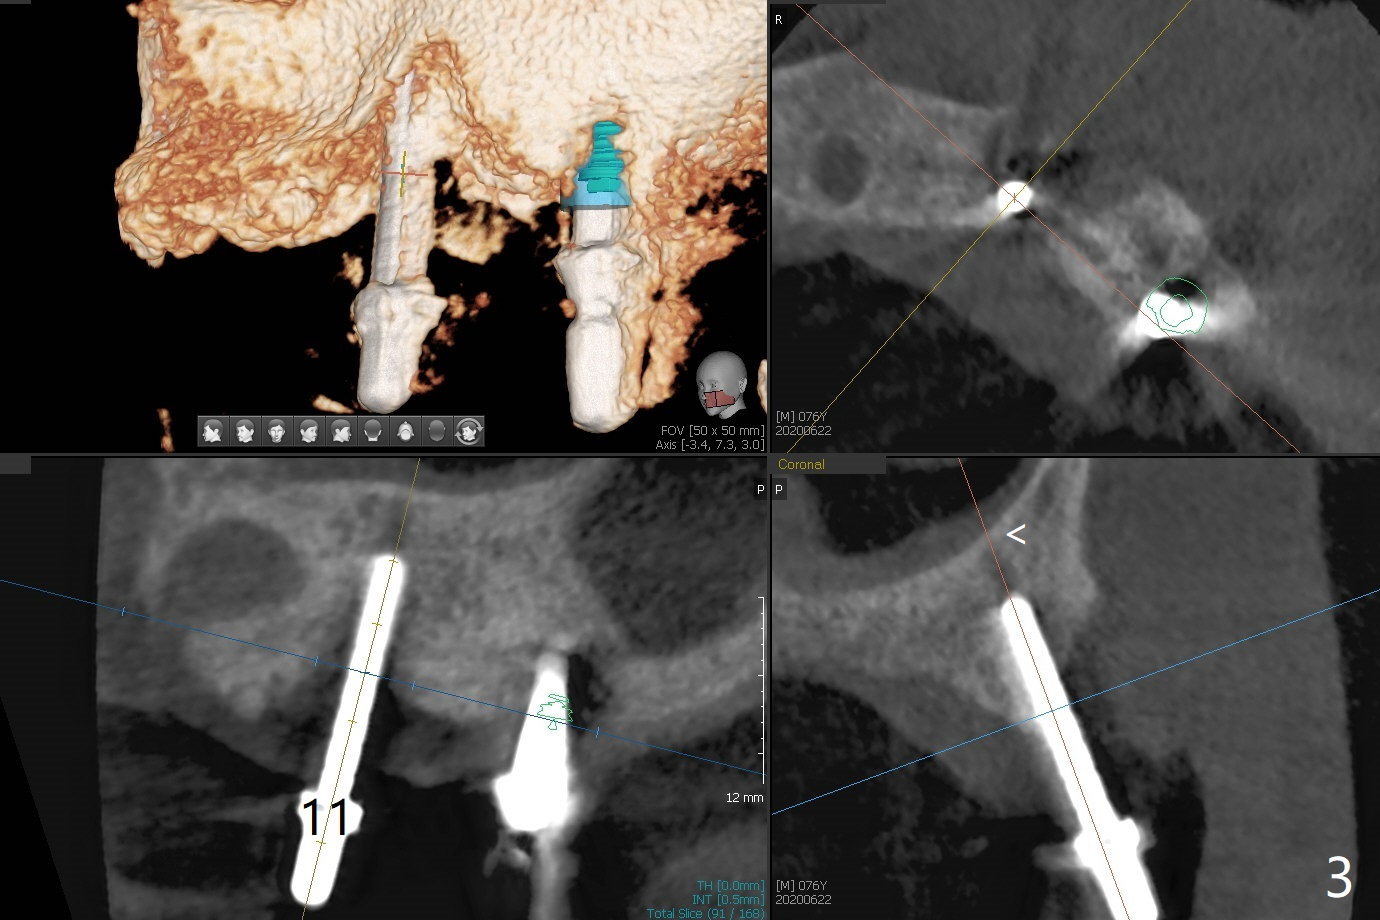

Osteotomy at #13 starts blindly (no incision or tissue punch) with bone expanders. After insertion of parallel pins, intraop CT shows that it is palatal with apparently buccal low bone density (Fig.1); the osteotomy for implant (Fig.2 green) should be shifted buccal and tilted mesial (red, parallel to #11) with incision. In contrast the position, trajectory and depth (Fig.3 <) of the initial osteotomy are acceptable at #11. The implant will be placed as it is (Fig.4). After taking a postop PA (Fig.5), the implant at #11 is placed a little deeper to make sure its slightly subcrestal placement (including distal incision at #11). Following placement of 3.5x4 and 3 mm ball abutments at #11 and 13, cortical allograft with PRF is placed around the implants, especially buccal (Fig.6,7 <). After suturing, the profile of the ball abutments is too low for RPD retention. Due to gravity other than bone density, the number of ball abutments for the maxilla should be more than for the mandible. Soft reline is done to the patient's satisfaction. The retention of the upper RPD after soft reline is satisfactory without pain 7 days postop (Fig.8). The implant at #13 is loose nearly 3 months postop (Fig.9 *: bone loss). The implant is removed while the ball abutment is untightened; the sinus floor is present. It appears that a longer and larger implant is necessary; a 4.5x10 mm dummy implant is unable to be seated deep or achieve primary stability (Fig.10). After sinus lift with 3 mm Bicon osteotome without bone graft, the dummy implant accomplishes the 2 tasks mentioned above (Fig.11). However there is no corresponding definitive implant in stock. Implant system needs to be changed; with a change in implant driver, the depth control is lost. The final implant is placed deep (Fig.12). With back up, stability is lessened; a healing screw is placed; with collagen plug, the wound is sutured (Fig.13). The wound heals 1 week postop (Fig.15). The RPD is soft relined. Retention from the ball abutment at #11 is apparently critical. The RPD and #11 implants (4 months postop) are stable, while the wound at #13 heals 1.5 months postop (Fig.15). There is space around the implant 5.5 months postop (Fig.16 *). The 5x10mm SM implant is found to be loose upon uncover and removed. After debridement, 5.3x8 mm SM and 5.5x9 mm IBS dummy implants are inserted without stability, while 6x9 mm definitive one with stability (Fig.17). Cortical allograft is placed in deficiency areas (*). The osteotomy has no roof (sinus floor), but the sinus membrane is intact. Small amount of bone graft (Fig.18 *) is placed before implantation. There appears to be bone around the new implant (Fig.19 (3D sagittal section) *).